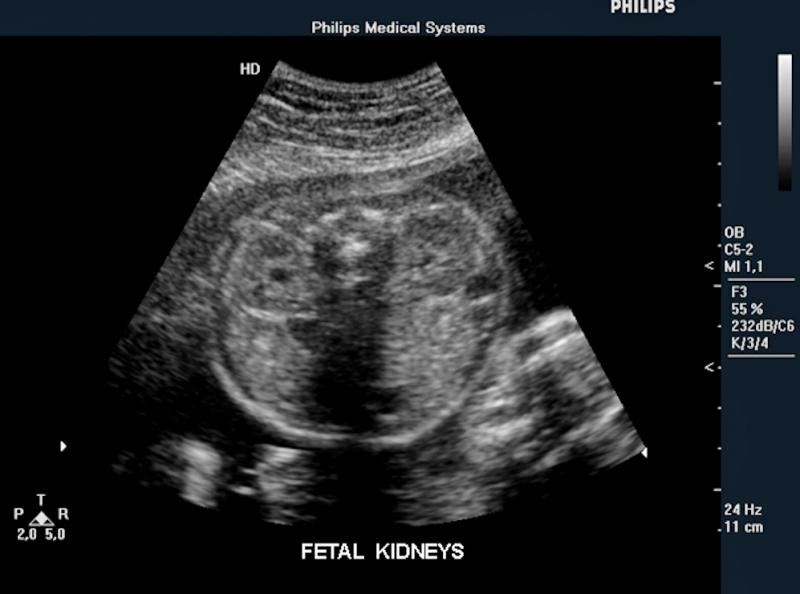

Below is a collection of prenatal ultrasound pictures from the Imaging Technology News (ITN) archive. Use the arrows to click through the image gallery. It includes transvaginal ultrasound images and fetal echocardiogram images. Fetal imaging is referred to by many names, including pregnancy sonograms, pregnancy ultrasound, endovaginal ultrasound, obstetric ultrasound, OB ultrasound, baby ultrasound, prenatal ultrasound. Fetal heart ultrasound is also called baby echo or prenatal echo.